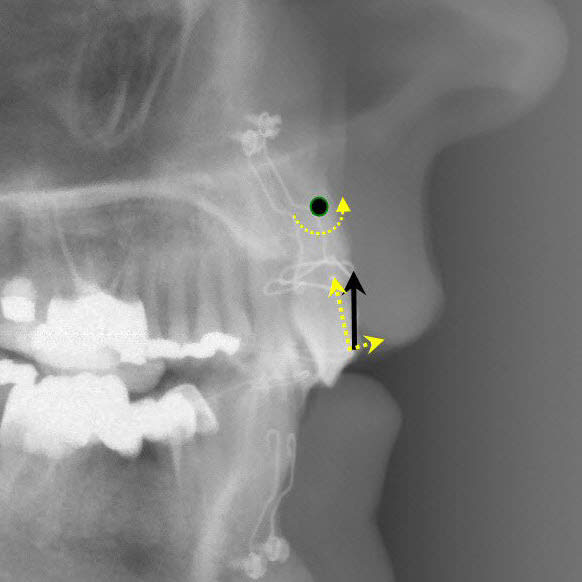

Ce qui est intéressant dans ce cas, c'est que l'ingression s'est accompagnée d'un recul radiculaire des incisives non explicable par la mécanique utilisée (très simple par ailleurs).

Le fil que j'avais utilisé était rond, ce n'est pas lui qui a pu reculer les racines.

Ce n'est pas non plus l'effet de la direction de la force d'ingression, comme je le montre sur le schéma. On aurait dû avoir une vestibuloversion coronaire pas un recul des apex. Le centre de résistance de la dent était très haut parce qu'il y avait un support osseux très réduit.

Il faut donc chercher ailleurs l'explication, et c'est là qu'on pourrait faire un parallèle avec le cas de Jeff…

Ce que j’ai voulu monter avec le cas d’ingression c’est l’action méconnue de l’orbiculaire des lèvres. Je ne vois pas d’autre explication à ce recul des apex qu’une pression de sa part sur la corticale vestibulaire et un « glissement » de la racine le long de cette corticale.

Mon schéma de bio mécanique en page 1 de ce post n'est pas bon pour expliquer le recul de l'apex ?

> Mon schéma de bio mécanique en page 1 de ce post n'est pas bon pour expliquer

> le recul de l'apex ?

Si, sauf que ton centre de résistance me semble un peu bas, mais surtout que cela impose un fil excessivement rigide bloqué au niveau molaires pour empêcher la vestibuloversion coronaire. Dans le cas que j’ai montré, le fil était très fin, en NiTi .012 (0,3mm).